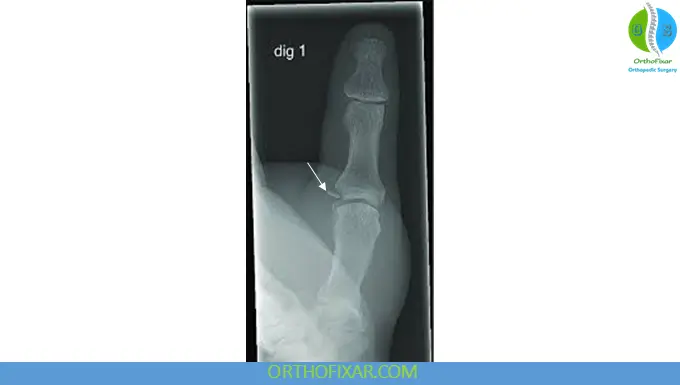

- X-ray: Detects avulsion fractures